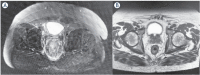

Background: Electrochemotherapy (ECT) is a minimally invasive and safe treatment gaining positive and long-lasting antitumoral results that are receiving the attention of the scientific community. It is a local treatment that combines the use of electroporation and the administration of cytotoxic drugs to induce cell death in the target tissue. ECT is largely used for the treatment of cutaneous and subcutaneous lesions, and good results have been reported for the treatment of deep visceral tumors. The latest literature review is provided. Moreover, in line with its development for the treatment of visceral tumors in this article, we describe a novel approach of ECT: endoscopic treatment of colorectal cancer. Endoscopic ECT application was combined with systemic chemotherapy in the treatment of obstructing rectal cancer without prospective surgery. A good response after ECT was described: concentric involvement of the rectum was reduced, and no stenosing lesions were detected.

Conclusions: Clinical studies have demonstrated that ECT is a very effective treatment for tumors of different histologic types and localizations. Endoscopic treatment for gastrointestinal cancer is an innovative application of ECT. The combination of systemic treatment and ECT was safe and highly effective in the treatment of colorectal cancer, especially when obstructive, giving the patient a significant gain in quality of life.